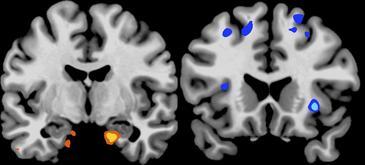

Numerosas investigaciones han relacionado el aumento de la obesidad en los países industrializados con una constante disminución en las horas de sueño. Pero los mecanismos cerebrales implicados en el proceso aún no han sido suficientemente estudiados.Ahora un equipo de investigadores de la Universidad de California ha demostrado que la falta de sueño causa cambios en el cerebro asociados con un mayor deseo por alimentos altamente calóricos. Los resultados del estudio se publican hoy en la revista Nature Communications. Según explica a SINC Matthew P. Walker, autor principal del trabajo, “estudios previos habían demostrado que las personas que duermen menos, tienden más al sobrepeso y obesidad. Nuestro estudio pretende lograr una mayor comprensión de los posibles mecanismos cerebrales que explican esta relación”.El equipo de Walker llevó a cabo un experimento en el que participaron 23 individuos sanos (13 de ellos mujeres) y examinó su actividad cerebral tras una noche completa de sueño y después de una noche sin dormir.Durante la medición de la actividad cerebral, llevada a cabo con un escáner de resonancia magnética, los participantes fueron decidiendo cuanto querían comer de un total de 80 elementos que les fueron mostrados.Estructuras cerebrales profundas“Nuestros resultados han demostrado que las regiones del cerebro relacionadas con la toma de decisiones de alto nivel quedan embotadas por la falta de sueño a la hora de elegir alimentos. Por el contrario, las estructuras profundas del cerebro que controlan la motivación y el impulso se amplifican”, dice el investigador.Además –añade– “un hallazgo adicional interesante fue que a los participantes privados de sueño les apetecían más los alimentos ricos en calorías”.Walker indica que esta menor actividad cerebral en regiones que controlan las buenas decisiones, en combinación con la amplificación en aquellas más relacionadas con la recompensa inmediata, encaja bien con las teorías de que la falta de sueño favorece el aumento de peso y la obesidadPor ello, el científico opina que "promover que la gente duerma un número adecuado de horas puede ser una buena fórmula para facilitar el control de peso en la población, favoreciendo los mecanismos cerebrales que gobiernan una buena elección de los alimentos".